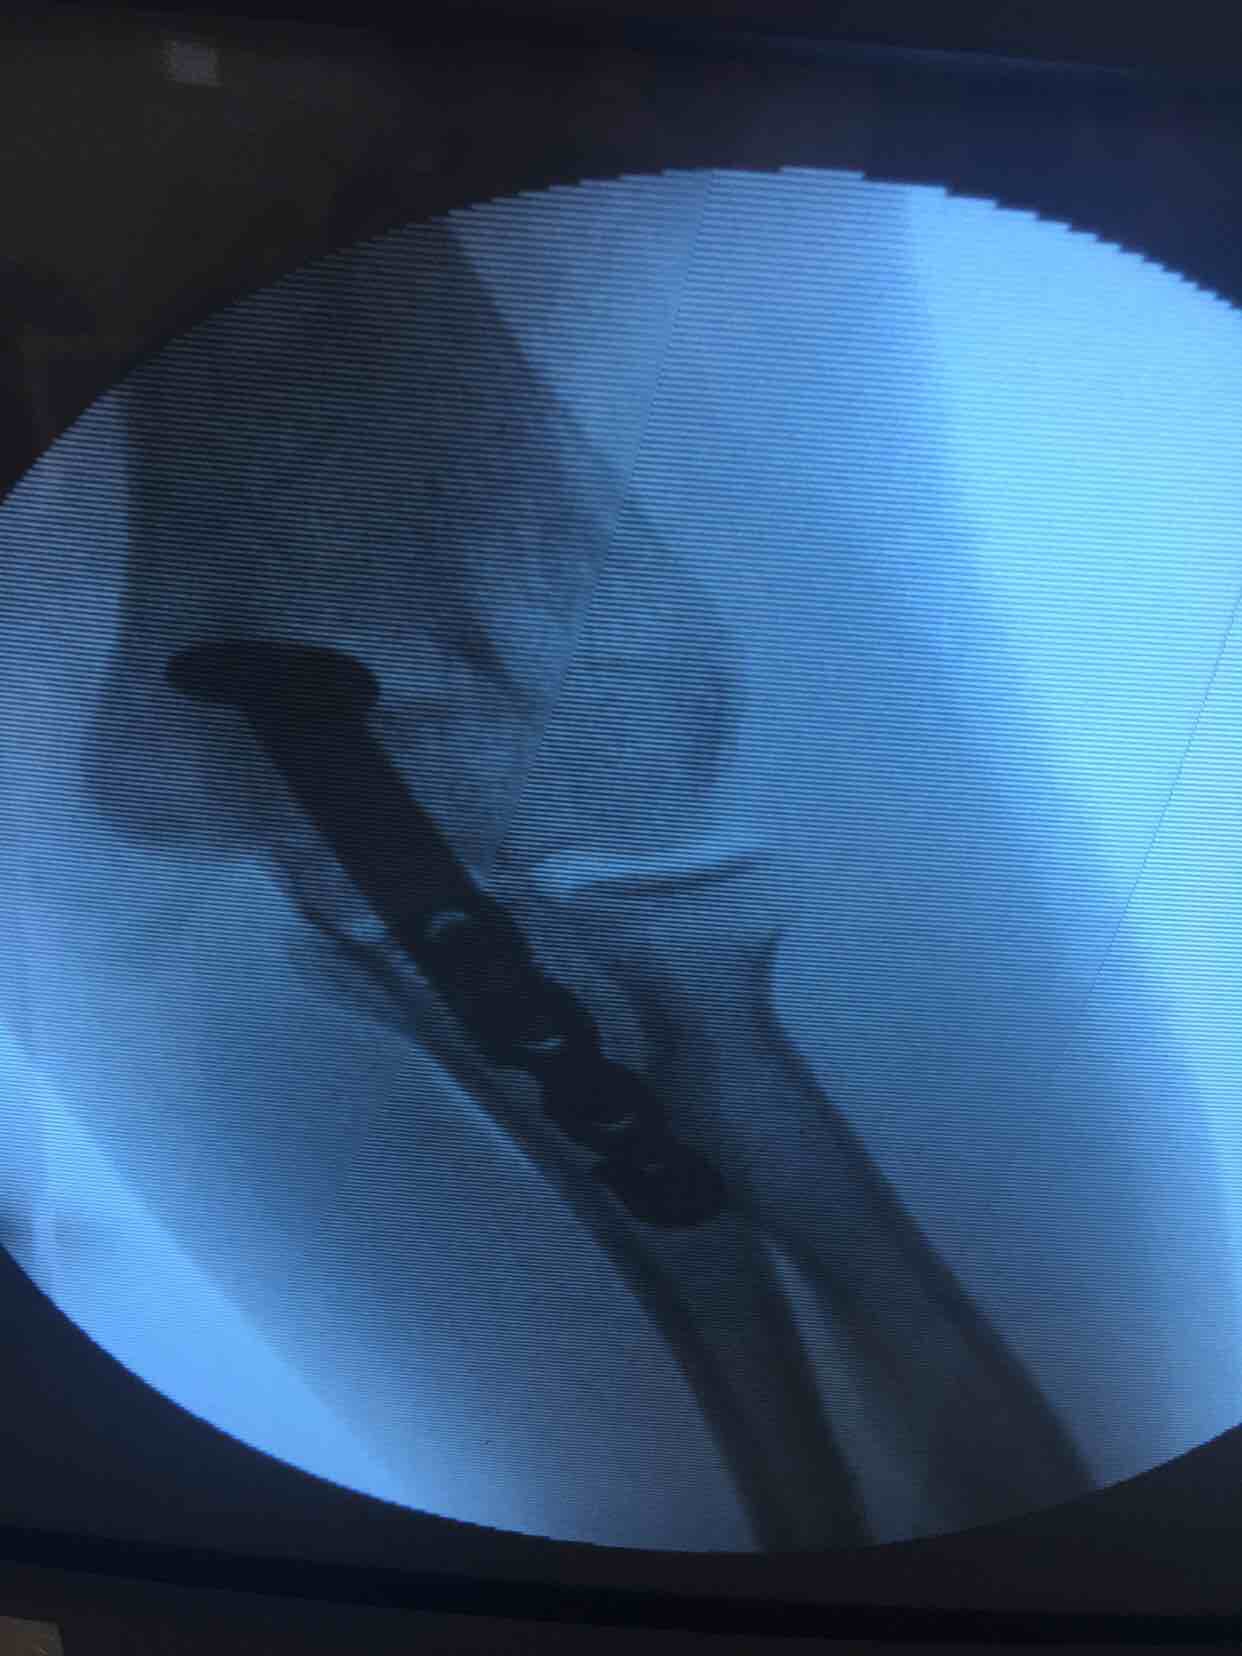

尺骨鹰嘴骨折(切复内固定术)

诊断右尺骨鹰嘴骨折在臂丛麻醉下行切复内固定术,术后抗炎,消肿等处理。